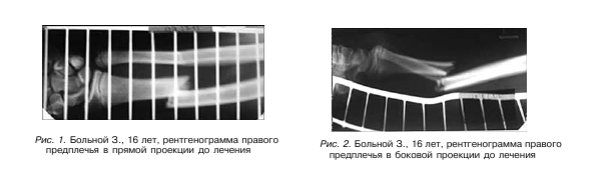

Клинический пример. БольномуЗ., 16лет, с диагнозом: закрытый диафизарный перелом костей правого предплечья со смещением фрагментов, - выполнена операция - остеосинтез АВФ стержневого типа (рис. 1,2).